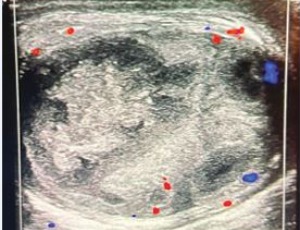

Abstract Testicular abscess and global testicular infarction are rare consequences of epididymo- orchitis, particularly when appropriate antibiotic treatment is given. -